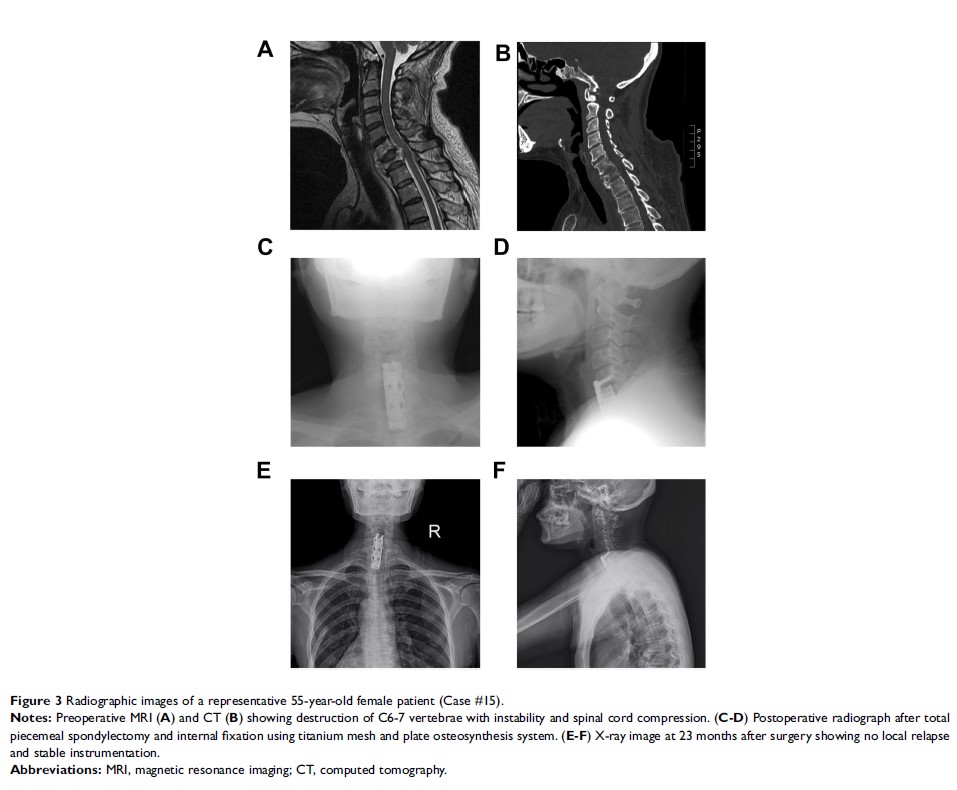

胃癌脊柱转移患者的手术结果和预后因素